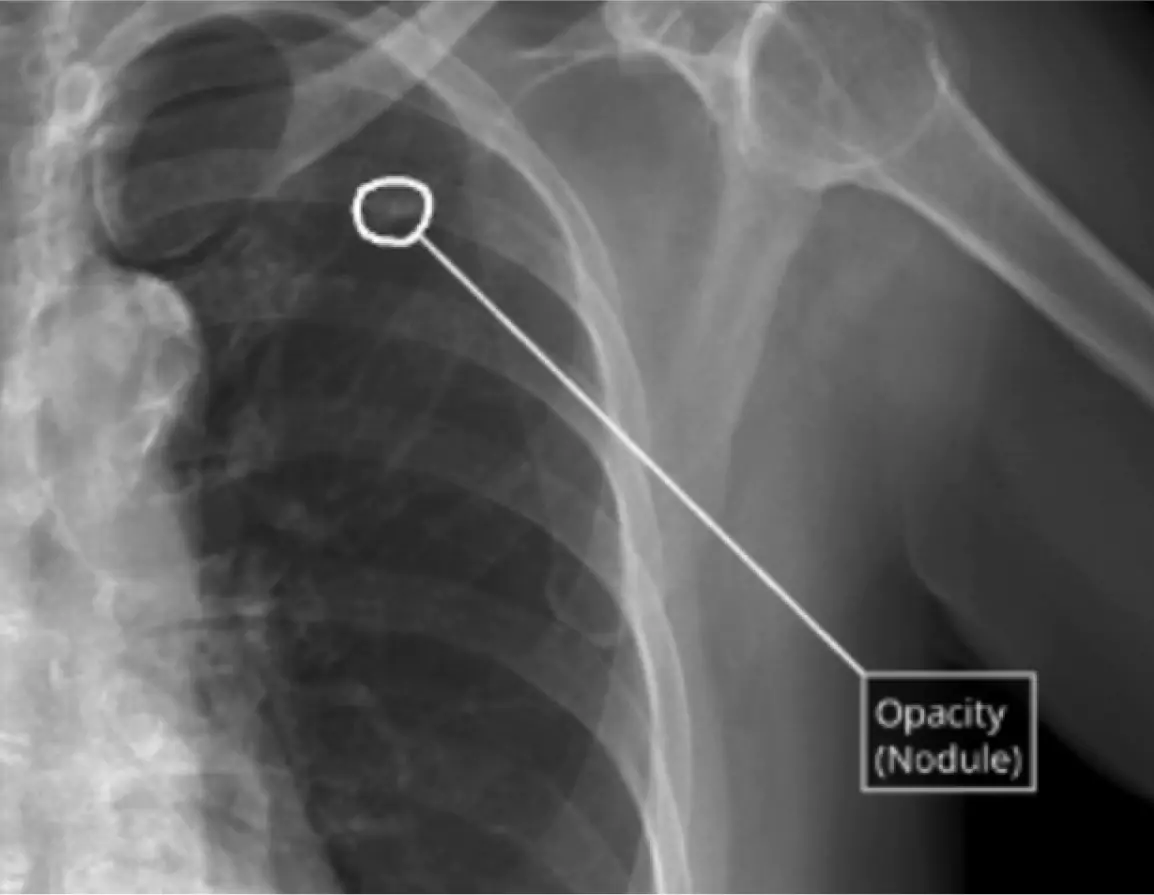

AI for CXRs

World’s most widely used AI for comprehensive chest X-ray reporting. Pre-read assistance in 20 seconds with findings across lung, heart, pleura, mediastinum, bones & diaphragm.